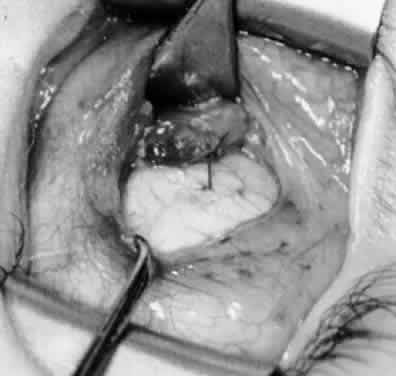

Fig. 10. The inferior oblique muscle is placed on the Green muscle hook. The exposed insertion is ready for myotomy, myectomy, disinsertion, placement of sutures for recession, or removal for the extirpation procedure.

Fig. 11. Sutures are placed into the insertion of the inferior oblique muscle before it is sectioned from the globe for the recession procedure.